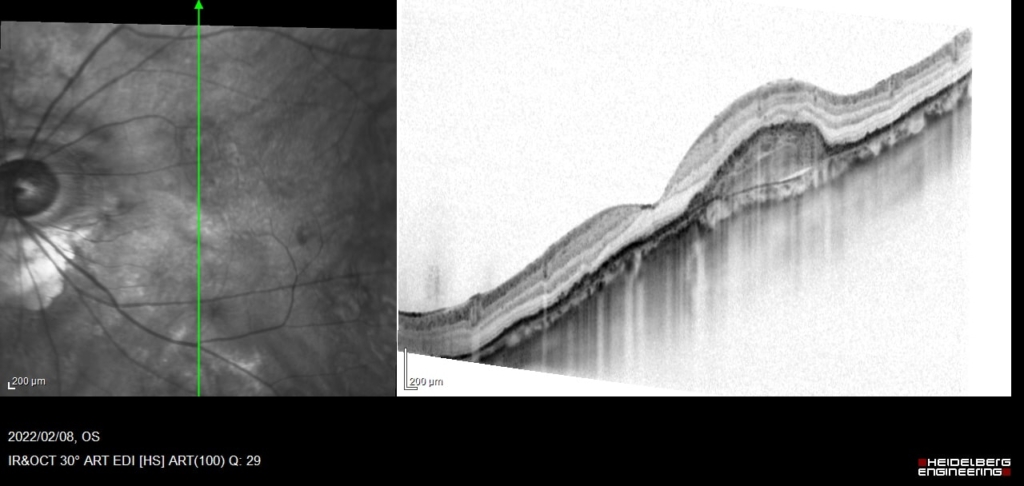

線維血管性 PED fibrovascular PEDは、表面は不整なドーム状隆起を呈する。内部は不均一な中等度から低反射を示し、漿液や出血成分、線維性の層状の中等度反射が混在している。これはRPE下のCNVの存在を示す。

RPE下に広がるCNVとBruch膜の間に間隙が生じており、同部位でBruch膜が後方に偏位している。間隙は浸出液の貯留による。